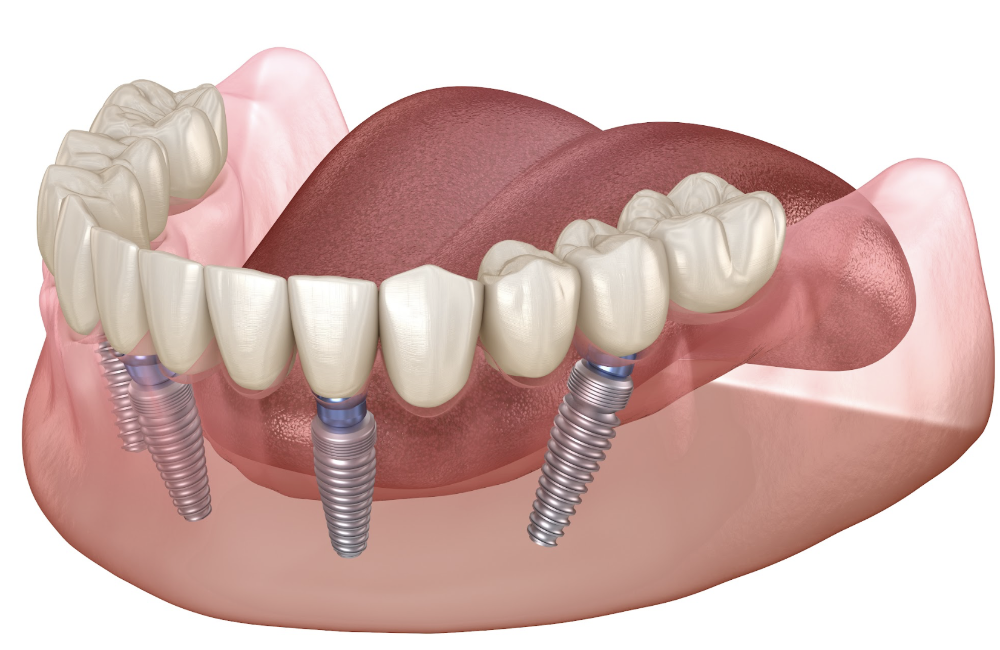

Our hybrid team specializes in restoring confidence through state-of-the-art implant solutions, including All-on-4 and fixed hybrid dentures. From consultation to the final smile reveal, you’ll be cared for by a skilled, coordinated team focused on your comfort, long-term health, and natural results.

Whether you’re looking to replace multiple missing teeth or upgrade from traditional dentures, Dr. Parr and his hybrid experts deliver life-changing results — all under one roof, with sedation options available for a calm, comfortable experience.